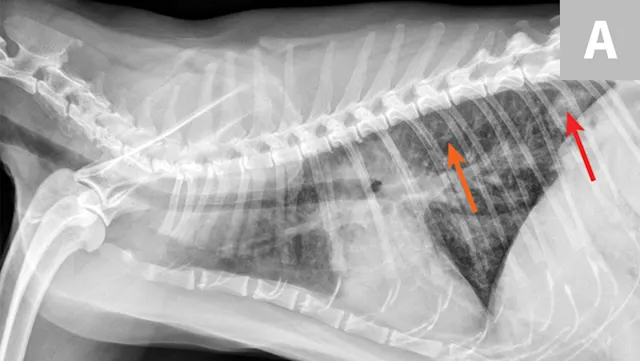

FIGURE 1A

Congestive heart failure. Note the pleural effusion (arrows).

Overt cardiomegaly may be understated on radiographs because of changes in internal diameter that do not affect the overall cardiac silhouette. Vertebral heart score >9.3 supports a CHF diagnosis.1 Pulmonary venous congestion can be absent, and pulmonary arterial distension may be appreciated. The presence of pleural effusion with simultaneous pulmonary infiltrates is supportive of CHF (Figure 1).2